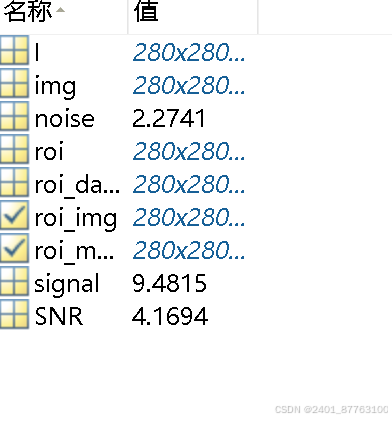

这是我自己计算出来的SNR,你可以利用几幅不同的图片重复以上步骤,然后进行对比,可以将SNR归一化后对比效果更好。